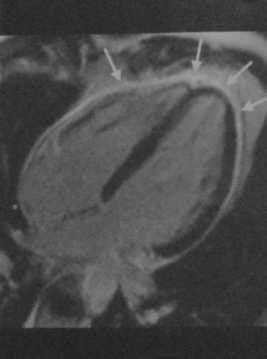

Контрастно-усиленная последовательность обратного восстановления GEчерез 15 мин после введения 0,2 ммоль/кг Gd-DTPA. Четырехкамерный срез демонстрирует выраженное усиление перикарда (стрелки).